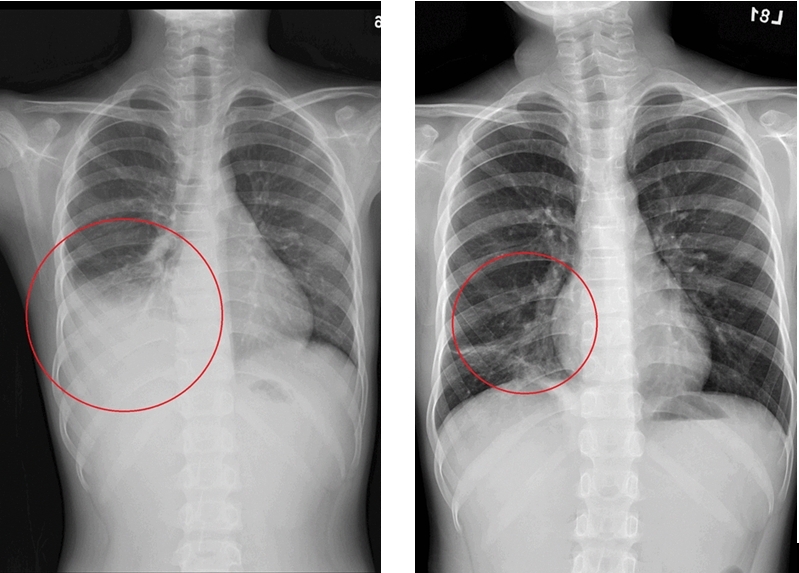

經抗生素治療後,許小弟仍然高燒未退,甚至出現肺炎擴散及肋膜積水的情形(左);

先後使用口服四環黴素及喹諾酮類藥物進行治療,肺部積水也明顯減少(右)。

但病情萬變,經抗生素治療後許小弟仍高燒未退,甚至出現肺炎擴散及肋膜積水的情形。經小兒感染科吳秉昇醫師透過黴漿菌抗生素的調整,當晚許小弟即逐漸退燒,一週後平安出院,後續胸部X光追蹤亦發現右下肺炎及肋膜積水已改善。

黴漿菌肺炎以抗生素治療為主,過往多半使用紅黴素,但衛福部疾管署《感染控制雜誌》研究曾指出,台灣兒童感染的黴漿菌已對紅黴素產生6成以上的抗藥性,必要時須改以其他抗生素,如四環黴素或喹諾酮類抗生素治療。以許小弟為例,醫療團隊評估其症狀較為嚴重,且之前曾使用紅黴素治療,可能有紅黴素抗藥的情形,因此先後使用口服四環黴素及喹諾酮類藥物進行治療,發燒才逐漸改善,四天後肺部積水也明顯減少,病況穩定。吳秉昇醫師強調,醫師開立抗生素藥物會考量其年齡與臨床症狀嚴重度,並參考醫療指引進行治療,因此家長應遵從醫囑,按處方開立的劑量與時間讓孩童服用。